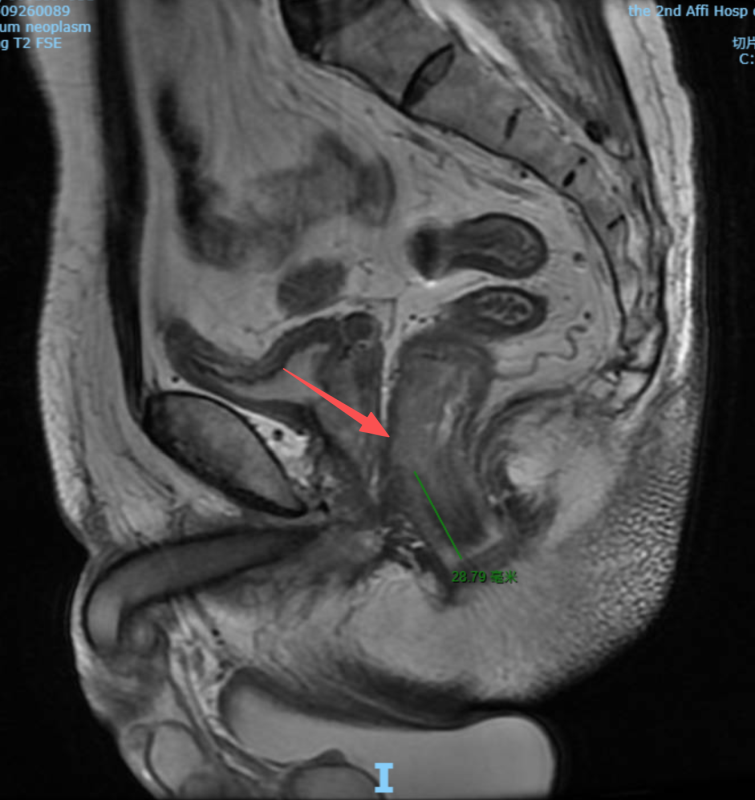

• 在医学发展的长河中,每一次技术的突破都意味着无数患者命运的改写。当直肠癌肿瘤逼近肛门仅剩约3厘米,许多患者面临的是“保命”与“保肛”之间的艰难抉择。然而,在温州医科大学附属第二医院(以下简称“温医大附二院”),来自江西的赵先生和陆女士,却在达芬奇机器人手术的辅助下,成功实现了肿瘤的完整切除与肛门的完美保留。这不仅是一场技术上的胜利,更是一次对生命尊严的守护。他们的故事,正是温医大附二院在低位直肠癌保肛领域不断探索与突破的生动写照。

直肠位于人体盆腔深处,空间狭小,血管与神经分布密集。当肿瘤生长在距离肛门较近的位置(医学上称为“低位或超低位直肠癌”),手术既要彻底切除肿瘤,达到根治效果,又要尽可能保留肛门功能,一直是结直肠外科领域的难题。许多患者因此陷入“保命”还是“保生活质量”的两难境地。

在赵先生和陆女士的案例中,温医大附二院组织了由肛肠外科、影像科、病理科、放疗科、麻醉科等多学科专家组成的MDT团队,进行了全面的术前评估,为每位患者量身定制了“个体化保肛方案”。该方案在严格遵循肿瘤根治原则的基础上,最大限度地考虑了功能保留与术后生活质量的提升。

最终,由肛肠外科王中林主任团队主导,为两位患者实施了达芬奇机器人辅助下的直肠癌根治术。手术过程中,主刀医生坐在控制台前,精准操控机械臂,在极有限的空间内游刃有余地完成了解剖、分离、止血、缝合等一系列高难度操作。肿瘤被完整切除,肠道成功吻合,肛门结构与功能得以完美保留。术后,两位患者恢复迅速,均在术后第七天顺利出院,重返正常生活。